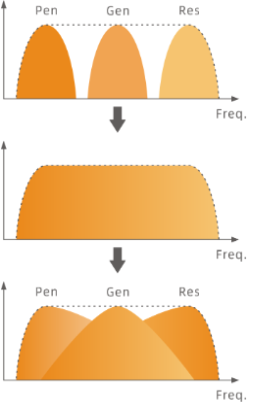

Dynamic analysis of Doppler echo spectrum enables the system to capture effective signal in both low and high frequency range. Precise control and fusion of these signals contribute to optimal image with better combination of resolution and penetration.